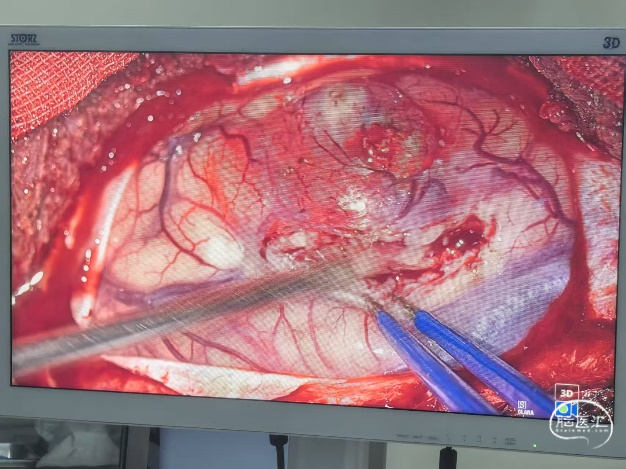

手术过程照片:

手术过程照片: